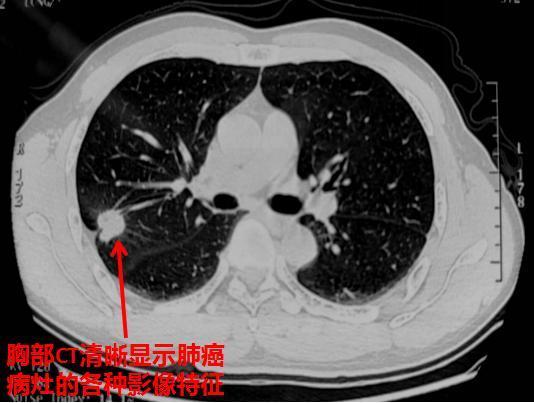

胸部ct清晰显示肺癌病灶的各种影像特征